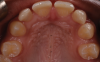

(4.) Pretreatment retracted occlusal photograph showing the multiple diastemas.

Figure 4

A 16-year-old female patient presented with the chief complaint that she was dissatisfied with the appearance of her anomalous maxillary lateral incisors (teeth Nos. 7 and 10) and multiple diastemas (Figure 1 through Figure 4). She had been referred for restorative treatment after an initial consultation with the orthodontist. Her first restorative appointment was dedicated to data collection, which included a health history and physical examination as well as the acquisition of photographs (facial, dentofacial, dental), videos (chief complaint, F sound, S sound), vinyl polysiloxane (VPS) impressions, a panoramic radiograph, a bite registration, and a facebow registration. The clinical examination revealed that both of the patient's maxillary lateral incisors were peg-shaped. After a discussion about the risks and benefits of different treatment options, such as direct composite restoration, indirect composite veneers, and porcelain laminate veneers, she chose to have her maxillary lateral incisors treated with direct composite buildup restorations. The index cutback technique was chosen for this case instead of a freehand technique in order to create a new shape according to an ideal wax-up but also to be able to control the thickness of the enamel layer.7